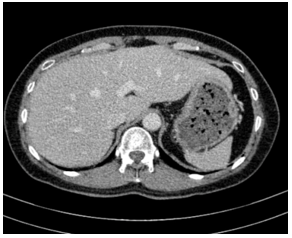

- Cắt lớp vi tính ổ bụng:

Hình 4:

Hình ảnh cắt lớp vi tính ổ bụng có tiêm: chưa phát hiện tổn thương nghi ngờ thứ phát

- Cắt lớp vi tính ổ bụng: Không phát hiện tổn thương bất thường.